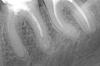

Kambriel Опубликовано 27 ноября, 2009 Автор Поделиться Опубликовано 27 ноября, 2009 Ну вот, дерни за веревочку- она и потянется... Была в другой клинике, консультировалась с ортопедом. Под металлическими коронками, говорит, мы можем увидеть только кариес, так что о состоянии стенок судить невозможно. Корни, сказал, нормальные. Но, как оказалось, 6-й зуб слева под коронкой почерневший (прикладываю фото, там видна темная полоса под коронкой- это зуб), а значит, мол, его опасно расцементировать. Сказал: "Вплоть до удаления. Так что вы должны быть готовы к тому, что если он развалится, то поставить имплантат." Но ведь меня не беспокоят зубы под коронками и то, что коронки короткие тоже. Жевала же 22 года. Я их регулярно чищу. Меня- то волнует 7-й слева. А мне врач сказал, что 7-й нужно накрывать вместе с 6-м, чтобы они друг друга держали. Вопрос: разве не лучше поставить коронку только на 7-й зуб? Ведь если что случится с одним зубом, тогда надо будет снимать коронку и с другого. И не трогать вообще пока эти шестерки, что под коронками? Уважаемые врачи, что посоветуете? Вот фото: И еще визиограмма 6-й и 7-й, что со штифтом. Вот еще и корни отдельно. Ссылка на комментарий

Kambriel Опубликовано 27 ноября, 2009 Автор Поделиться Опубликовано 27 ноября, 2009 (изменено) оба зуба на рентгене можно и нужно спасать. перепломбировывать качественно каналы, делать культевую вкладку разборную в оба зуба и одиночные коронки (не нужно их соединять, они сами по себе будут отлично держаться - но удлинить коронковую часть зуба - необходимо) - по вкусу: от литой до м/керамической на цирконии. Неужели все так плохо?! Так вот же врач и предупредил меня, что перепломбировать каналы в почерневшем зубе (он как- то назвал это терминологически), может оказаться невозможным и сказал, что в принципе, можно пока и не снимать коронку. Что ж тогда ходить, пока корни не развалятся? А культевые вкладки из чего лучше сделать в моем случае. И что такое металлокерамическая на цирконии? Я думала, что существует металлокерамическая и безметалловая из ДЦ. P.S. Только я заикнулась про диоксид циркония, как вызвала сильное раздражение у доктора. Мол, сидит, умничает. И мне было сказано, что это я только слышала, что они самые крепкие, на самом деле это далекооо не так. Теперь боюсь даже заикнуться про культевую вкладку. Да еще разборную. Изменено 27 ноября, 2009 пользователем Kambriel Ссылка на комментарий